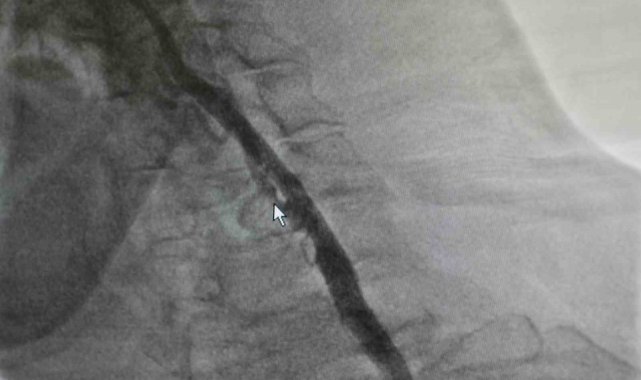

Samsun'da yaşayan Zekai Bozyel (71), 15 yıl önce bypass ve kalp kapak ameliyatı geçirdi. Rutin kontrolleri devam eden Bozyel, 20 gün önce kolunda güçsüzlük şikayetiyle nöroloji servisine yatırıldı. Yapılan tetkiklerde hastanın sağ boyun damarında yüzde 30, sol boyun damarında ise yüzde 90 oranında darlık tespit edildi. Sol taraftaki ciddi darlığın hastanın felç geçirmesine neden olduğu belirlendi. Hastanın daha önce kronik akciğer rahatsızlığı bulunması ve geçirdiği ameliyatlar nedeniyle anestezi açısından yüksek risk taşıdığı değerlendirildi. Bunun üzerine hastanın durumu kardiyoloji ekibi tarafından yeniden ele alındı. Akabinde Medicana International Samsun Hastanesi Kardiyoloji Uzmanı Dr. Öğr. Üyesi Ahmet Yanık, boyun damarında yüzde 90 darlık tespit edilen ve daha önce baypas ile kalp kapak ameliyatı geçiren hastaya ameliyatla kasıktan girerek uygulanan anjiyografik yöntemle stent yerleştirdi. Gerçekleştirilen başarılı müdahaleyle yeniden felç riskinin önüne geçildiğini belirtti.

Hastanın filmlerini inceleyip muayenesini yaptıklarını belirten Dr. Öğr. Üyesi Ahmet Yanık, "Zekai bey 15 yıl önce bypass ve kalp kapak ameliyatı olmuş, rutin takiplerinde devam eden bir hastamız. 20 gün önce nöroloji servisine yatıyor. İnme hikayesi ve kolunda güçsüzlük var. Yapılan tetkiklerinde boyun damarında darlık saptanıyor. Sağdaki boyun damarında yüzde 30, soldaki boyun damarında ise yüzde 90 civarında bir darlık var. Bu felç geçirmesine sebep olan bir darlık. Öncelikle ameliyat düşünüldü ancak kronik akciğer öyküsü ve diğer rahatsızlıkları nedeniyle anestezi açısından riskli bulundu. Biz damarın bu şekilde bırakılmasının daha riskli olacağını düşündük. Hastamızla görüşerek işlemi yapmaya karar verdik. Başarılı bir şekilde soldaki boyun damarına kasıktan girerek, herhangi bir kesi yapmadan anjiyografik olarak stent yerleştirdik. İşlem sonrası herhangi bir sorun yaşamadık ve hastamızı taburcu ettik. Müdahale edilmemesi durumunda daha ciddi bir felç riski söz konusuydu" dedi.